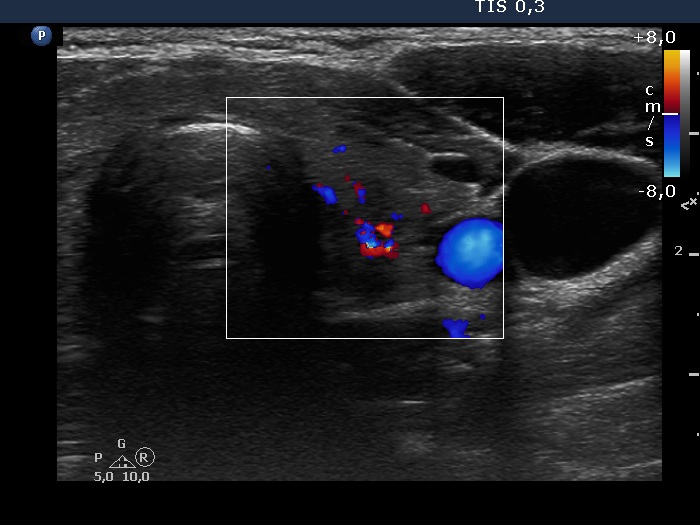

Consecutive patients with the final diagnosis of Hashimoto's thyroiditis - case 33 (228) (ultrasonographic picture 6)

Left lobe, transverse view, color Doppler mode. The vascularization is a bit increased.